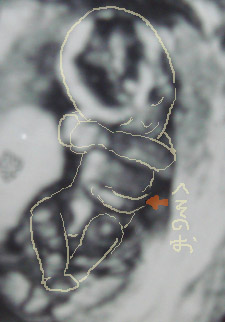

写真は17W1Dのもの。

まだ性別は分からなかったけど、へその緒がくっきりv

レナと繋がってるんだなーっと実感v